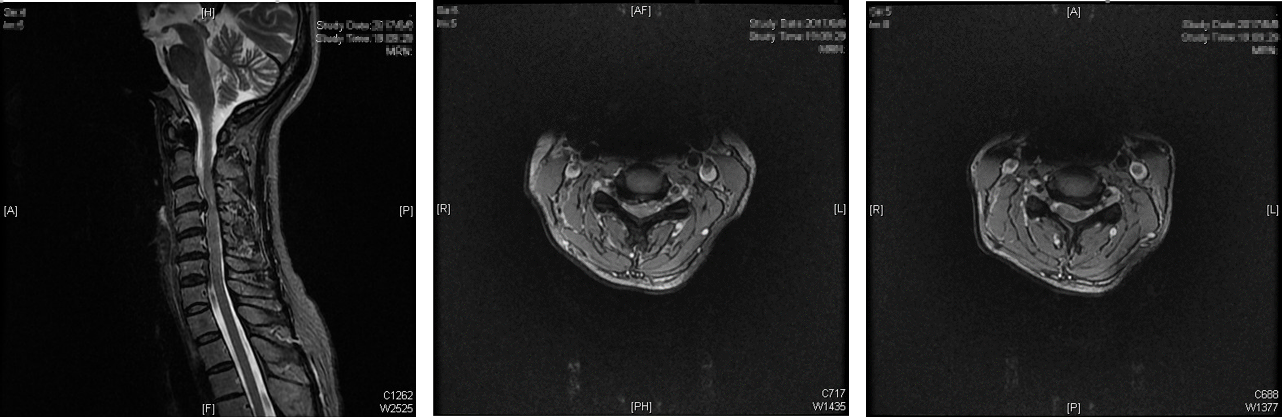

术前颈椎MRI:颈3-4,颈4-5椎间盘突出

患者就是天通苑社区的居民,1个月前右手麻木、无力到难以写字的程度,近20天逐渐出现左手麻木和双脚踩棉花感,近10天出现后背部麻木刺痛等症状。经神经内科武剑主任看诊,初步诊断为颈椎病合并脊髓病变。经与神经外科会诊,王劲副院长根据病人的查体以及影像判读,并再结合患者以往的病史,判断患者为严重颈椎病,颈椎间盘突出和骨赘压迫脊髓严重,累及颈3-4和颈4-5两个节段,只有通过手术切除突出的椎间盘和骨赘才能恢复神经功能。